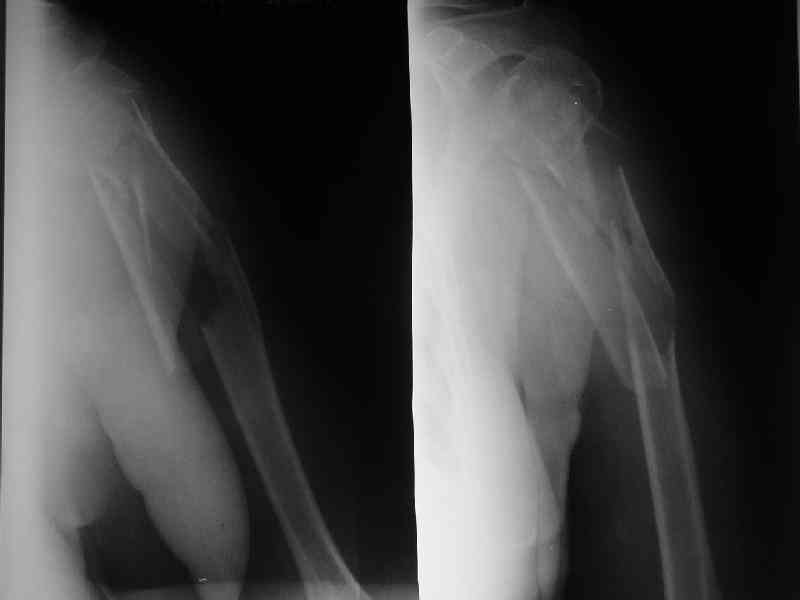

Добрый вечер!

Приложение как пример.

Что иллюстрирует этот пример? Это была множественная травма? Если это был изолированный перелом, то "золотой стандарт" - консервативное лечение.

Консервативно он уже лечился до этой операции в течение трёх с половиной месяцев.

А именно такой вариант операции выбран из экономических соображений.

вообще, торчашие в субакромиальное пространство шипы оставляют неизгладимое впечатление. Не думаю, что таким имплантом есть смысл гордиться

Снимок с имплантом из металла с памятью формы получился "sexy", но нарушены все каноны остеосинтеза. Потому что при комбинации двух ущербных систем одновременно повреждается внутри канальное и наружное кровообращение.